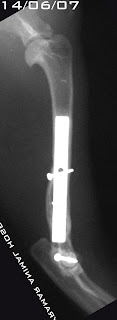

Una vez compensado su status respiratorio nos centramos en la fractura humeral:

Charlie presenta una fractura en esquina del hueso metafisario medial y desplazamiento de la epífisis respecto de la metáfisis en el resto de la placa de crecimiento:

Salter Harris tipo 2

Se reduce y estabiliza la fractura utilizando placa DCP de 2.7mm en medial + 6 tornillos 2.7mm y placa de reconstrucción 2.0mm + 4 tornillos 2.0mm

Se presenta la evolución radiografía en el tiempo y los grados finales de extensión y flexión de ese codo.